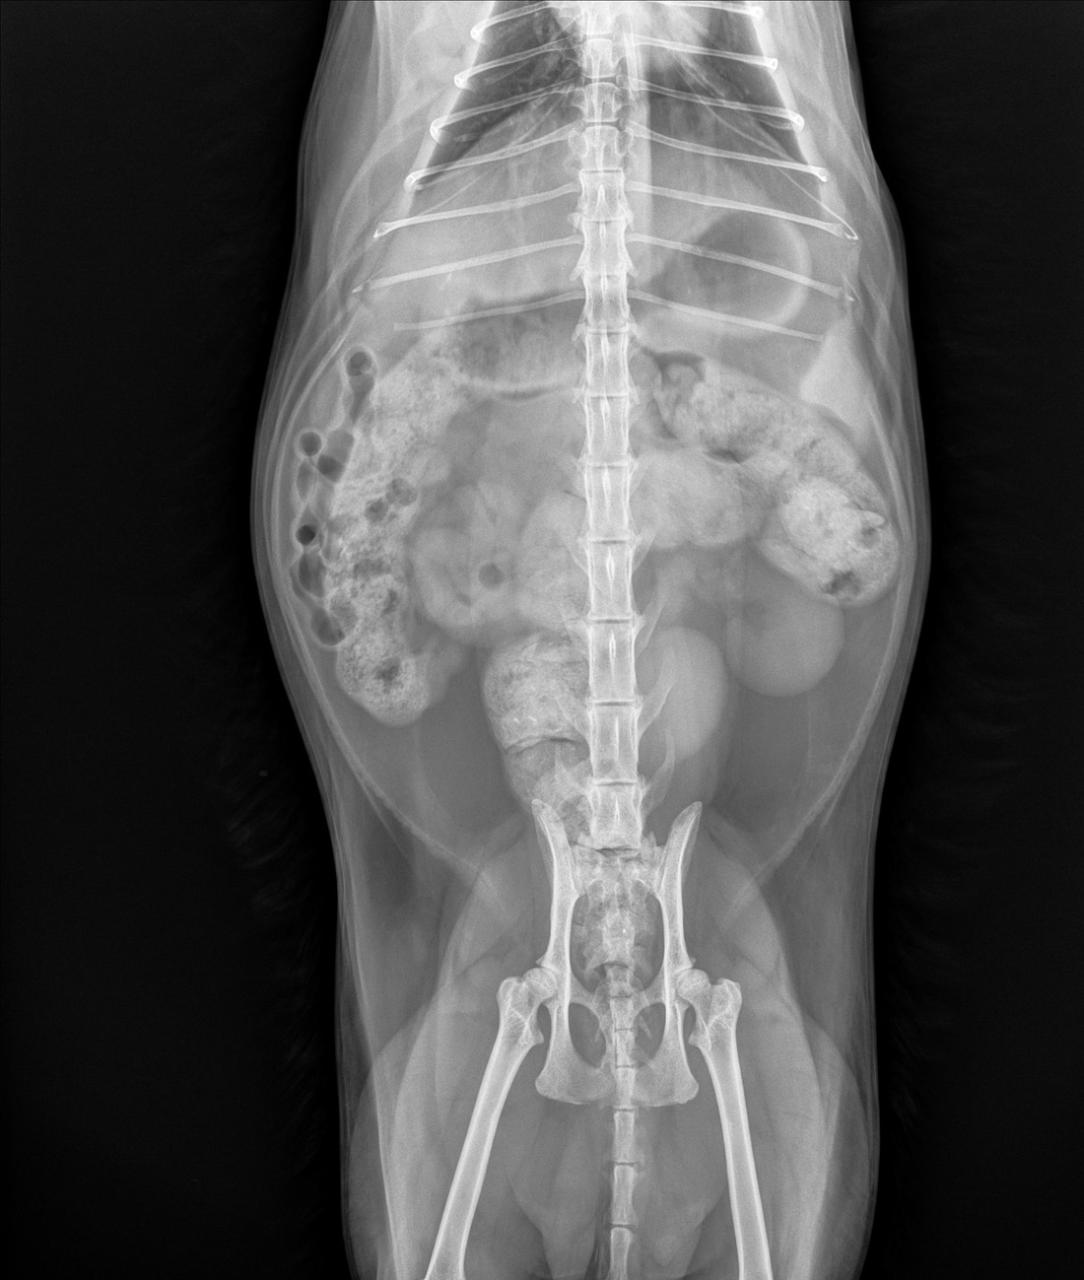

When we need to figure out what’s wrong with your pet, we routinely use x-rays to help identify the cause of the problem, rule out possible problems, or provide a list of possible causes. We may also use x-rays during a wellness exam to diagnose potential problems before they become serious.

X-rays provide valuable information about a pet’s bones, gastrointestinal tract (stomach, intestines, colon), respiratory tract (lungs), heart, and genitourinary system (bladder, prostate). We use radiology alone or in conjunction with other diagnostic tools. Interpretation of radiographs requires great skill on the part of the veterinarian.

We offer digital radiology (x-rays that are captured digitally rather than on film). This technology allows us to provide you with a quicker diagnosis for your pet. Plus, it uses less radiation than traditional x-rays.